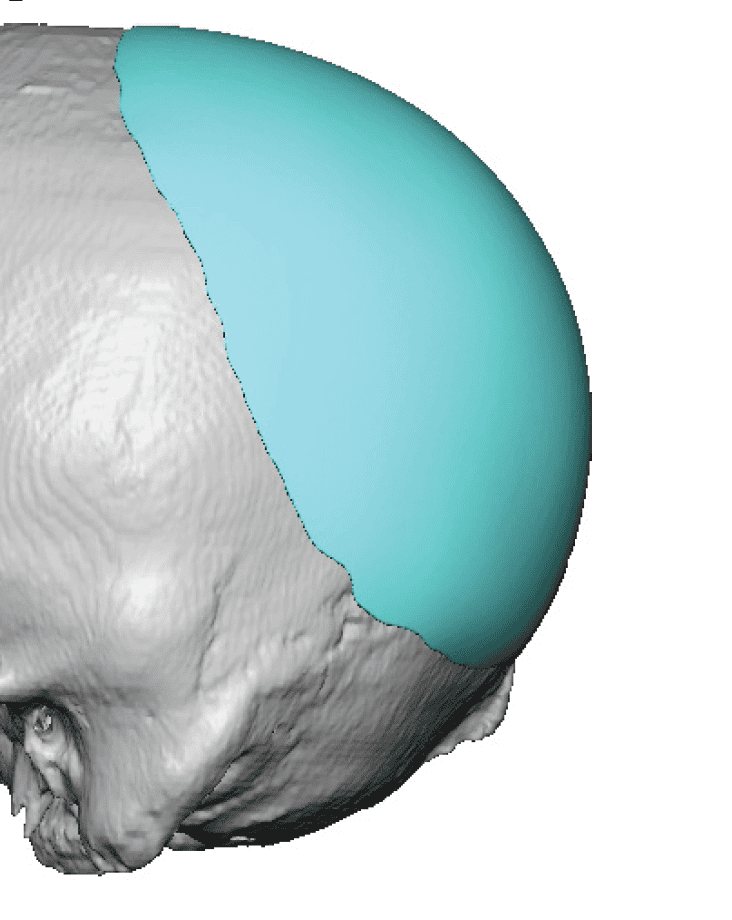

Desire for further skull augmentation after a primary skull implant.

Five years after an initial custom skull implant placement a new custom skull implant that increased the volume by 35% was placed.

Desire for further skull augmentation after a primary skull implant.

Five years after an initial custom skull implant placement a new custom skull implant that increased the volume by 35% was placed.